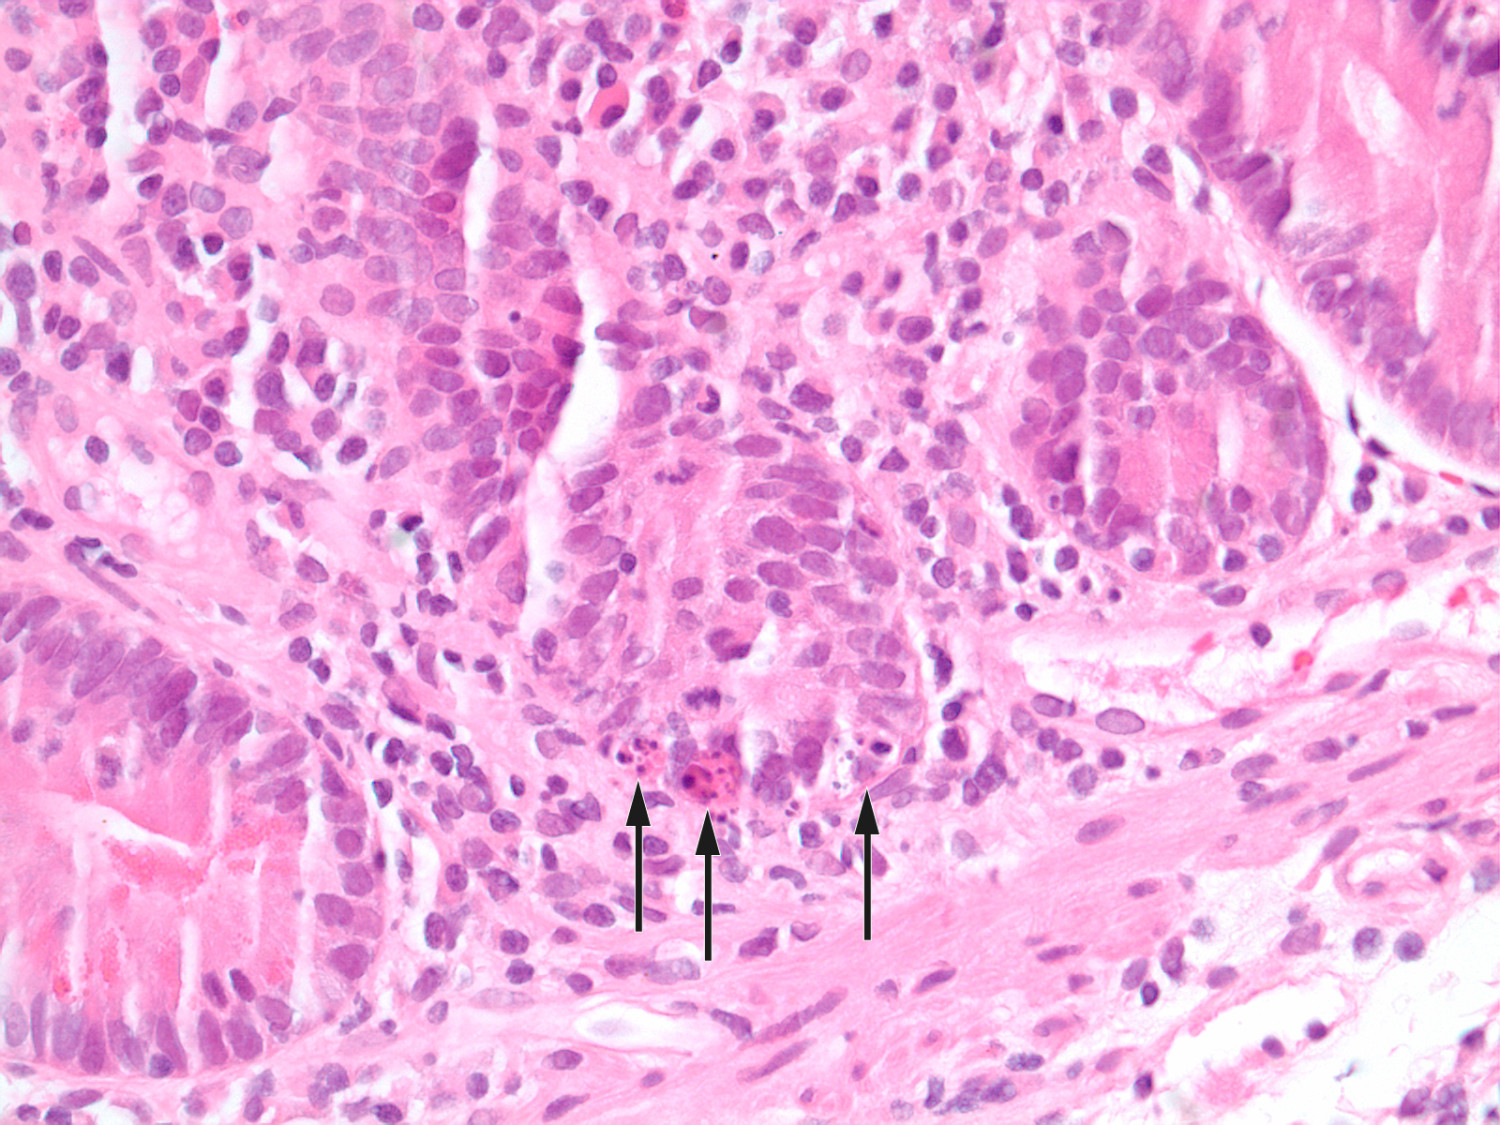

Det var ingen markant bedring etter de første dosene av vedolizumab. Gastroskopi, jejunoskopi og ileokoloskopi ble gjentatt uten signifikante makroskopiske funn. Mikroskopisk undersøkelse av alle tynntarmsegmenter viste total totteatrofi, økt mengde betennelsesceller (plasmaceller, lymfocytter og granulocytter) i lamina propria, apoptoser og fravær av begerceller i epitelet (figur 1 og 2). Det ble stilt spørsmål om autoimmun enteropati i svaret fra patologene.

Denne kasuistikken minner oss på å mistenke autoimmun enteropati hos pasienter med alvorlig malabsorpsjon, signifikant vekttap og autoimmun predisposisjon, der det histologiske bildet viser kombinasjonen av kronisk aktiv betennelse og totteatrofi i tynntarm. Cøliaki må utelukkes, enten ved negativ test for HLA-DQ2/DQ8 eller ved å vurdere behandlingsrespons på glutenfri kost. Selv ved manglende respons på glutenfri kost kan refraktær cøliaki være en mulighet, og monoklonalitet av T-celler i tarmbiopsi bør utelukkes ved flowcytometri (5) eller ved PCR-analyse for T-celle-reseptorgenrearrangering. Patologen er en viktig støttespiller, for eksempel kan mistanken vekkes ved et cøliakilignende bilde med tillegg av kronisk aktiv betennelse, apoptoser i kryptepitelet og fravær av begerceller (figur 1 og 2) (3). Positiv serumanalyse for antistoffer mot tarmepitelceller og begerceller kan styrke diagnosen, men er ikke diagnostisk (6). Andre differensialdiagnoser må utelukkes. Behandlingsresponsen er som regel god, selv ved steroidrefraktære tilstander (2).